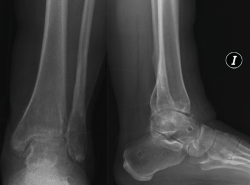

Figura 7. Caso de la Figura 6 con distracción articulada.